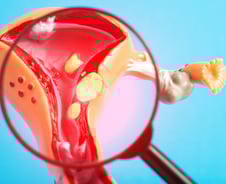

#. 20대의 미혼 여성 서영(가명)씨는 몇 달 전부터 아랫배가 볼록 나오자 '살쪘다'고 여기고 다이어트에 돌입했다. 하지만 어쩐 일인지 식이요법과 운동을 해도 살은 빠지지 않았고, 볼록한 아랫배도 그대로였다. 그러던 중 생리할 때가 아닌 시기에 출혈이 보였고, 산부인과를 찾아 생애 첫 산부인과 검진을 받았더니 자궁근종이 10개나 발견됐다. 서영씨처럼 자궁근종으로 진단받은 여성이 최근 우리나라에서 크게 늘었다. 건강보험심사평가원에 따르면 자궁근종으로 진단받은 환자는 2019년 43만5147명에서 2023년 63만8683명으로 약 46% 늘었다. 주로 가임기인 20~40대 여성에서 발병률이 눈에 띄게 증가했다. 흔하다고 대수롭지 않게 여기는 건 오산. 방치했다간 심각한 합병증까지 일으킬 수 있어서다. 과연 자궁근종은 왜 생기고, 어떤 문제를 일으킬 수 있을까. 자궁은 성인의 주먹 크기에 불과한데, 3㎏ 정도의 태아가 머물 수 있는 건 자궁 조직 대부분이 근육층으로 이뤄졌기 때문이다.